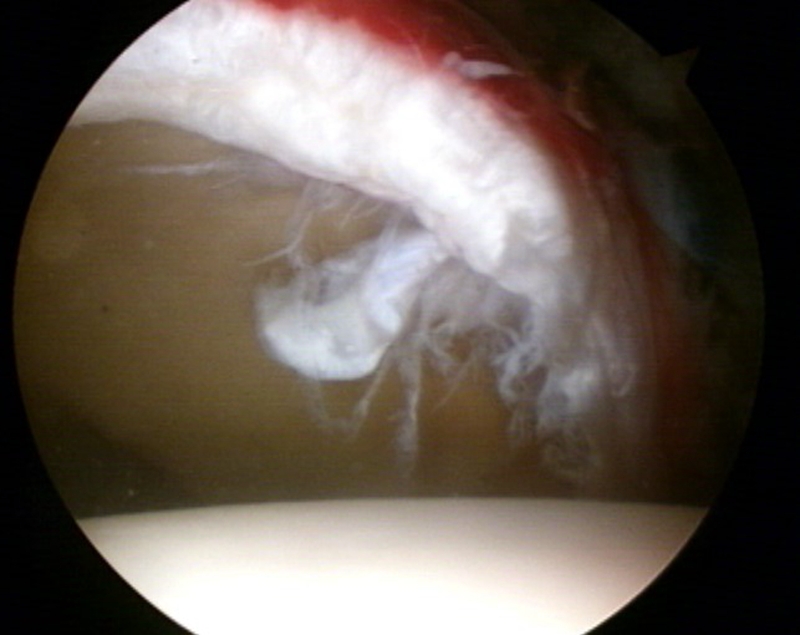

图4 髋关节镜术中图片,可见明显盂唇撕裂伴充血